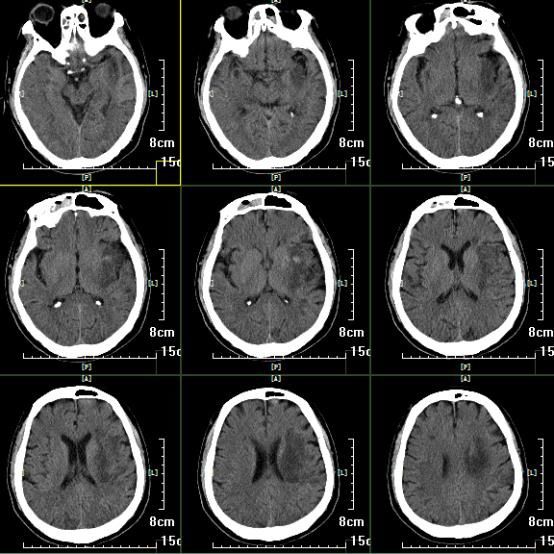

急诊头颅CT:颅内未见出血及大面积梗死。

术后即刻头颅CT

患者术后2周,复查头颅CT

患者术后2周,复查头颅CTA,左侧大脑中动脉通畅。